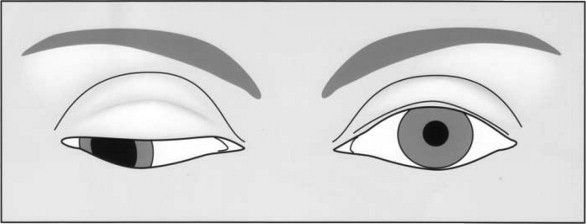

Нормальное зрение и диплопия

Различие монокулярной и бинокулярной диплопии